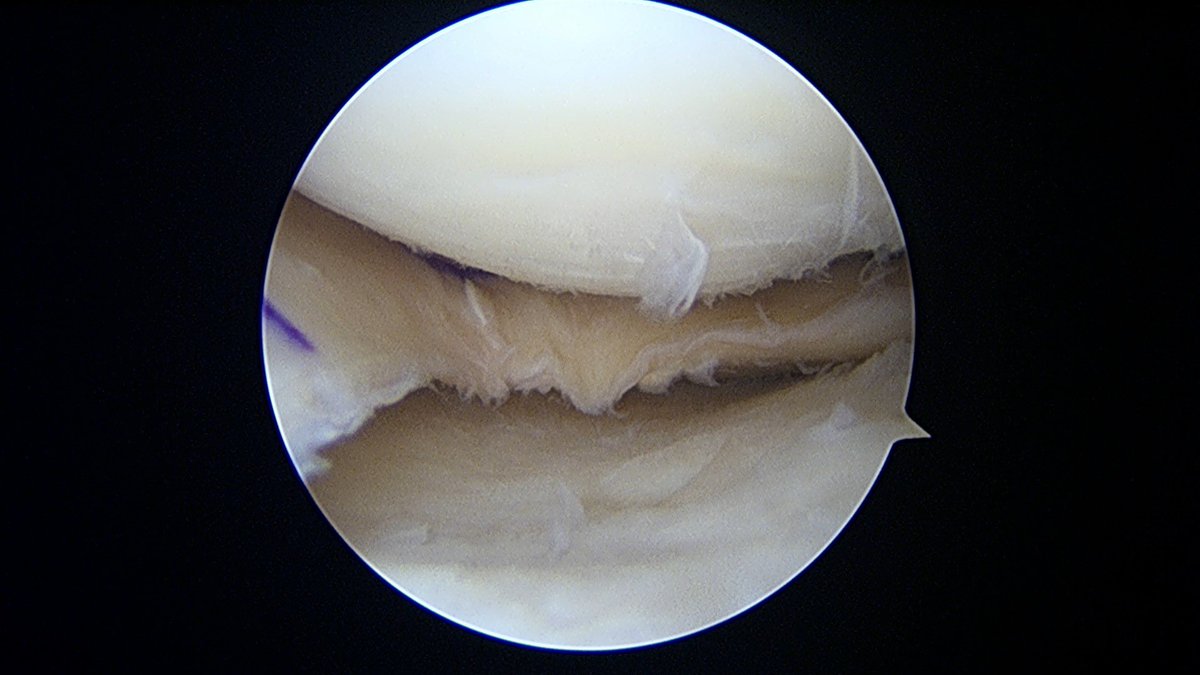

Incredible 1st 6 weeks of the Sports Surgery Fellowship in Perth. ACL's, PCL's, root repairs, multi-ligs, OATS, OCA, revision ACLs, Hip scopes. Not to mention the lifestyle. Highly recommend to those interested in soft tissue/joint preservation @BASKtrainees @58society @bota_uk